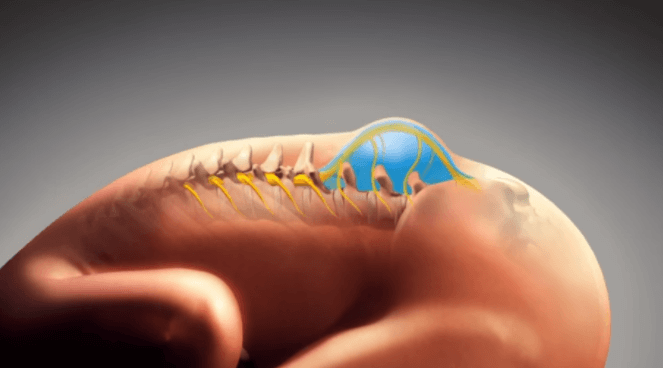

Mielomeningocele (espinha bífida)

A mielomeningocele é um tipo de espinha bífida. Espinha bífida é um defeito congênito que ocorre quando os…